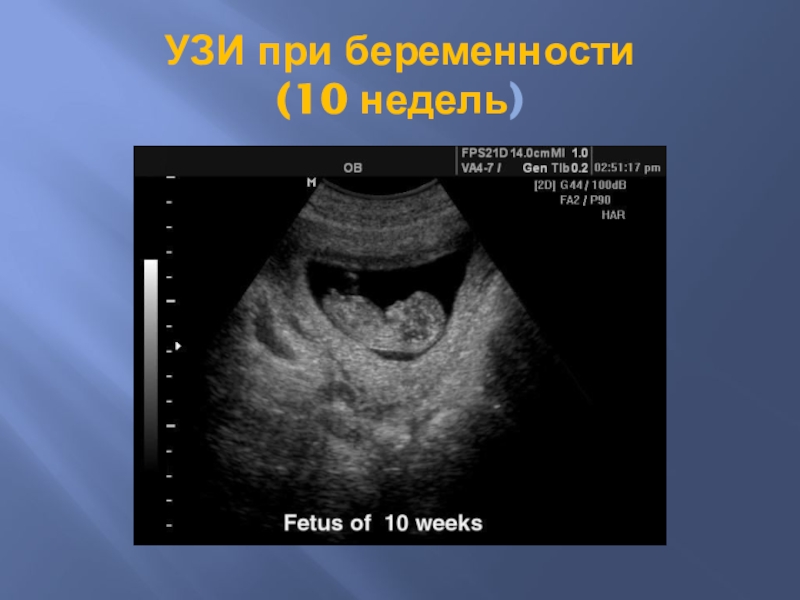

Слайд 58УЗИ при беременности (10 недель)

УЗИ при беременности  (10 недель)